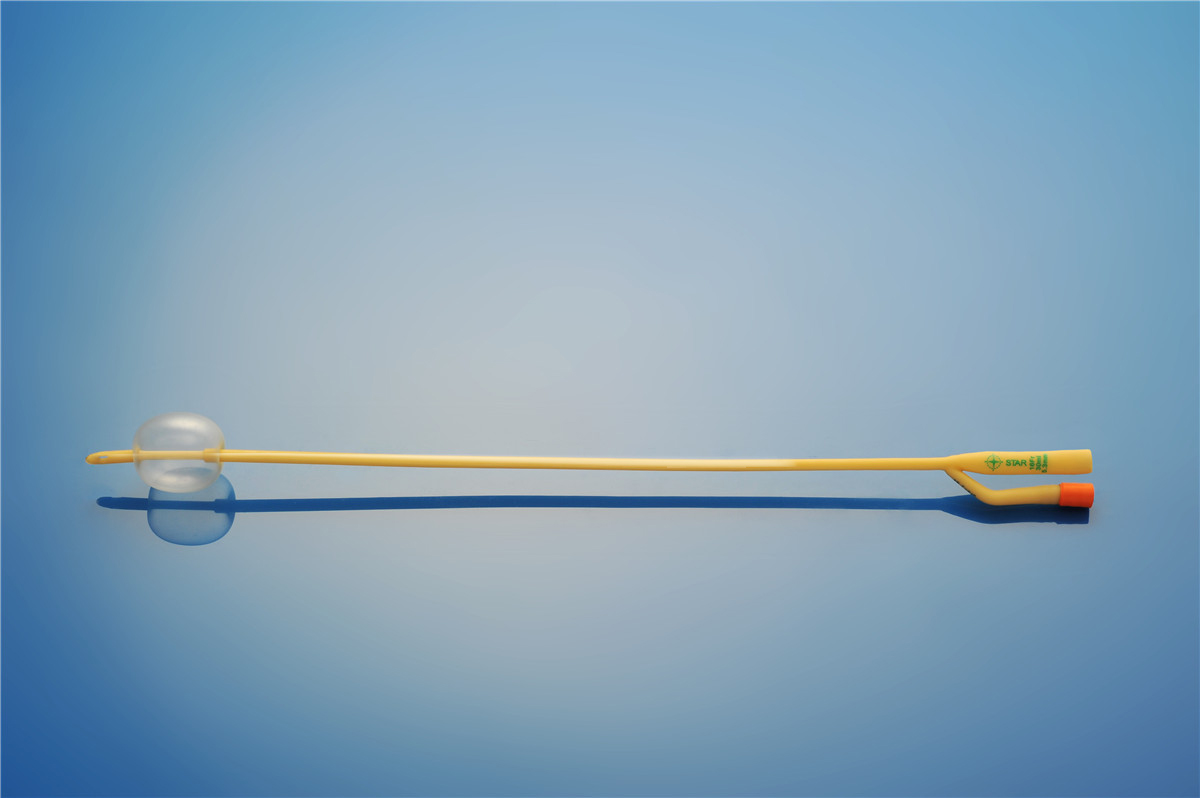

【產品名稱】一次性使用無菌導尿管(取樣型使用) 【型號】雙腔氣囊取樣型 【規格】:12FR-26FR 【主要結構、性能】由膠乳為主要原材料制成���,可配卡片����。

型號:雙腔氣囊標準型規格:雙腔氣囊標準型:12Fr(5-10mL)、12Fr(30mL)�、14Fr(5-10ml)、14Fr(30mL)���、16Fr(5-10mL)����、16Fr(30mL)、18Fr(5-15mL)�、18Fr(30mL)、20Fr(30mL)����、20Fr(50mL)���、22Fr(30mL)�、22Fr(50mL)...